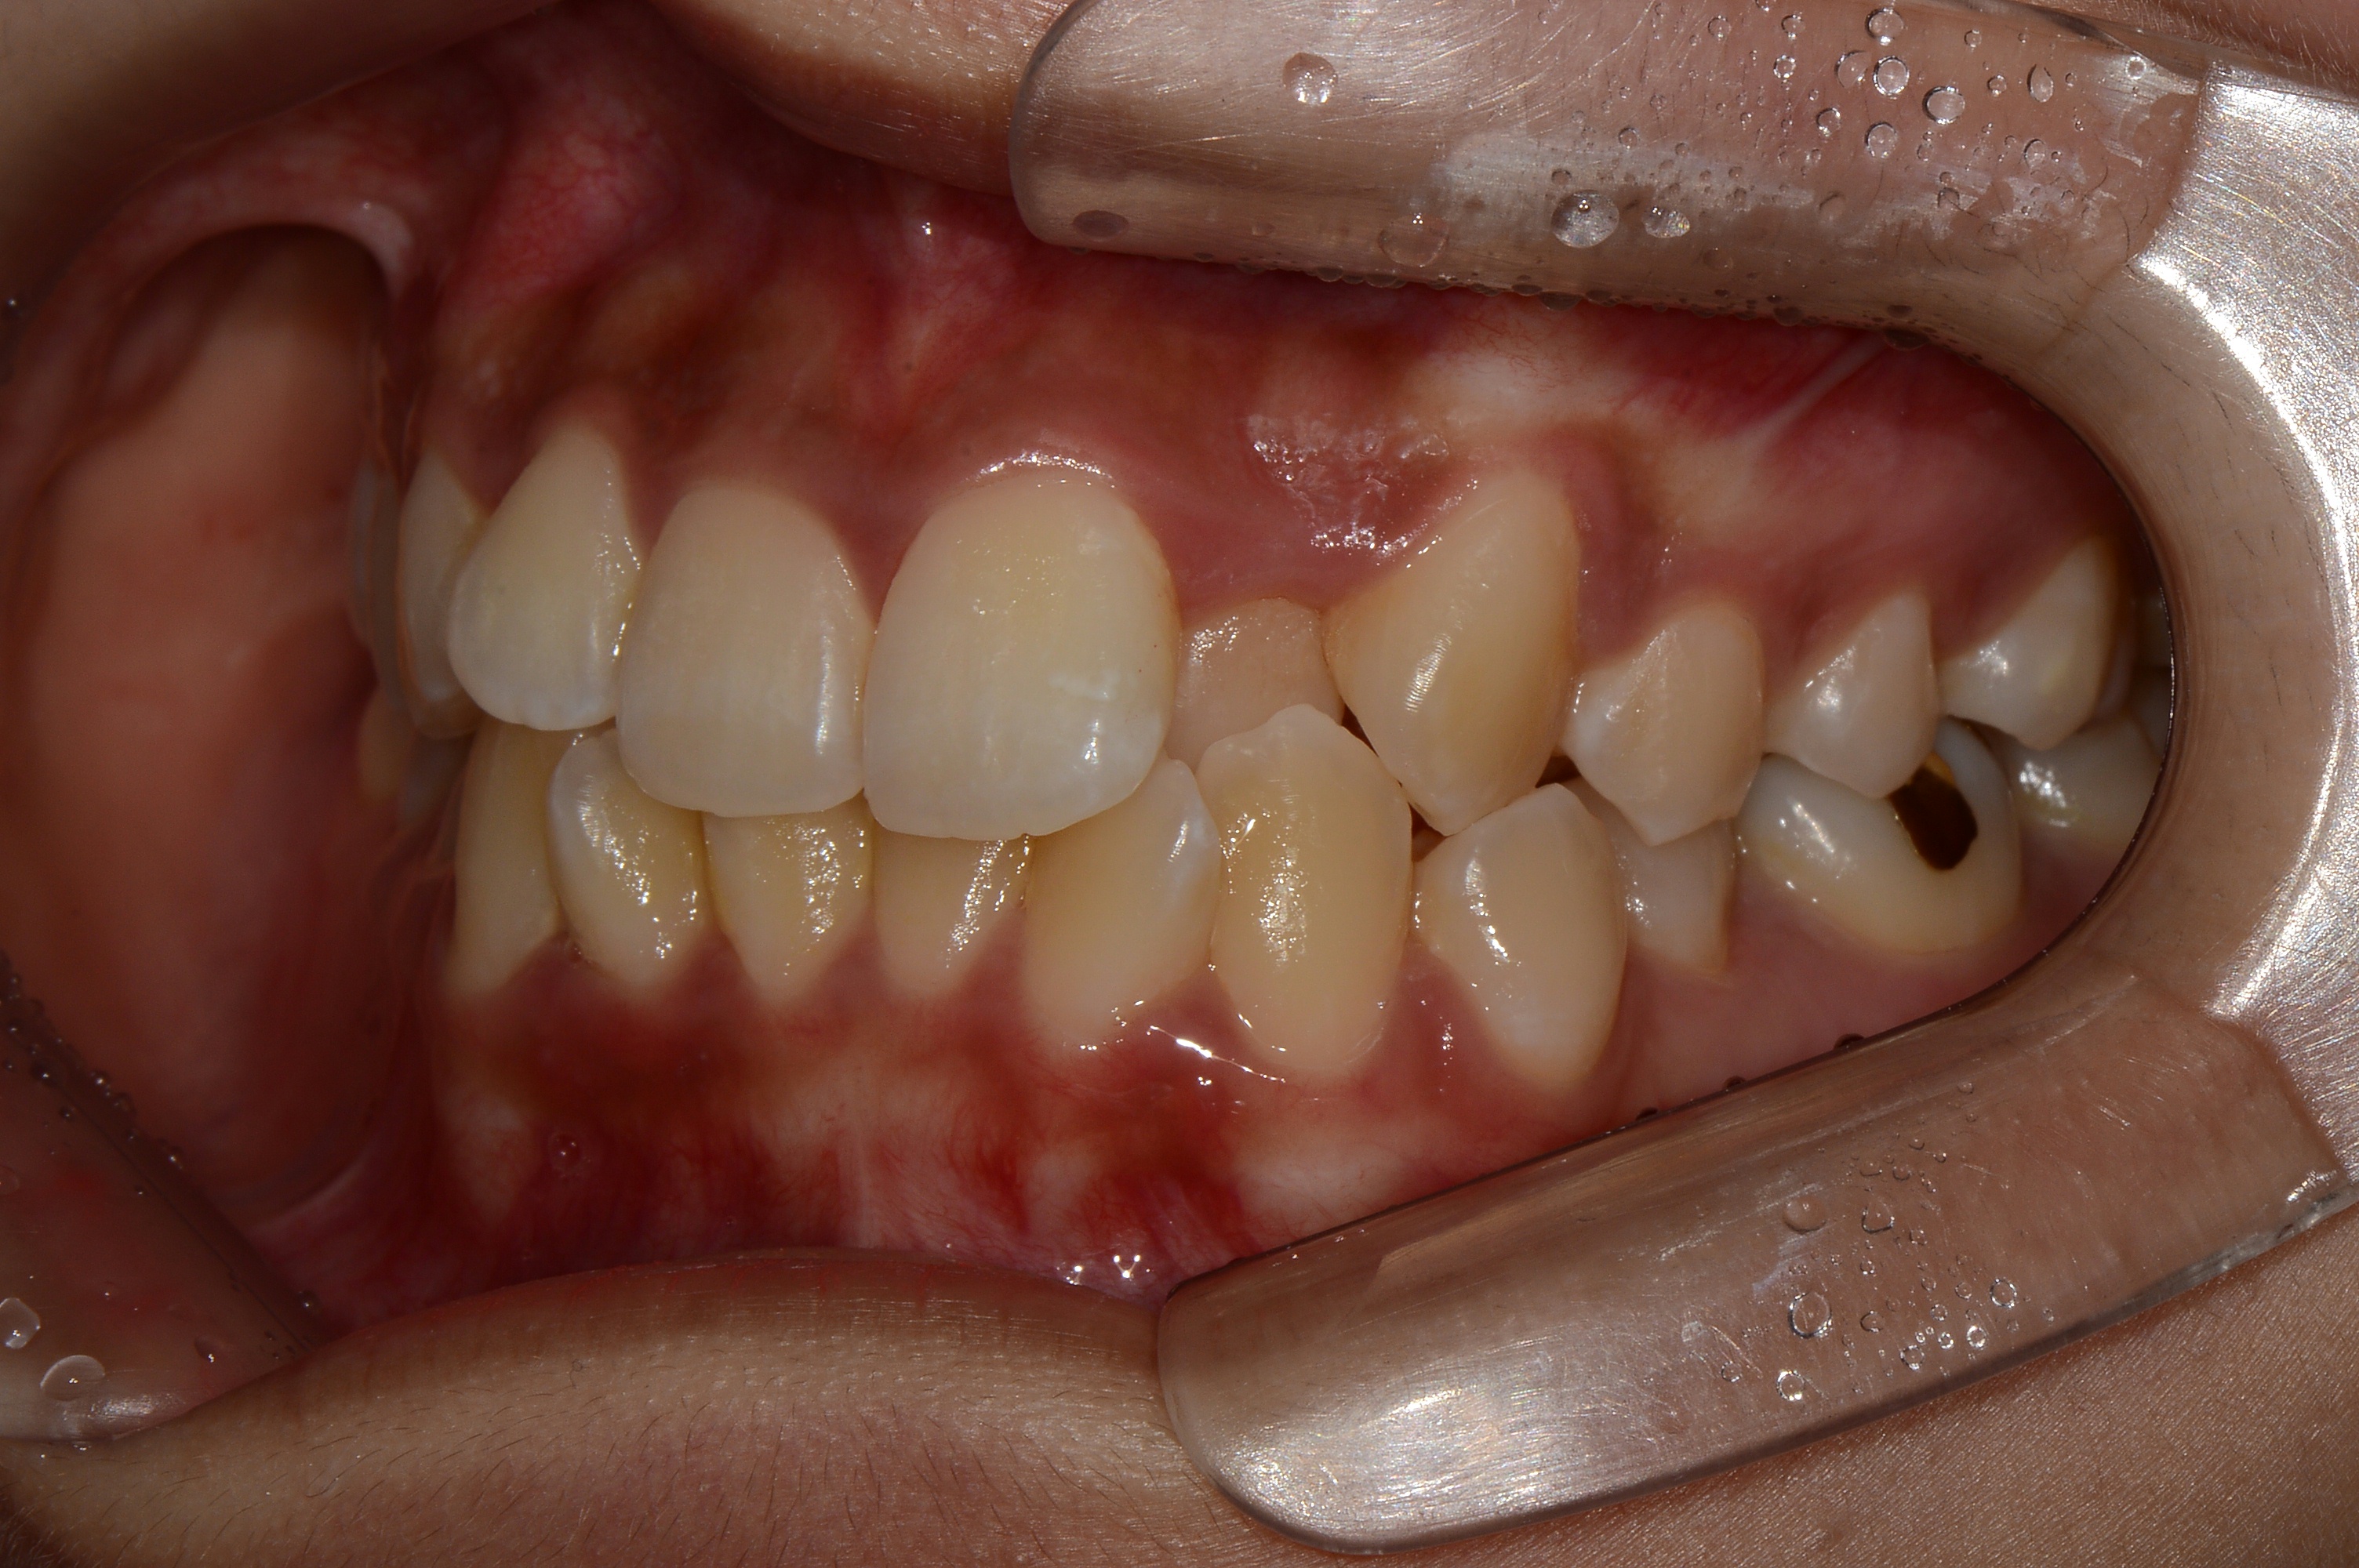

치료 전 사진입니다.